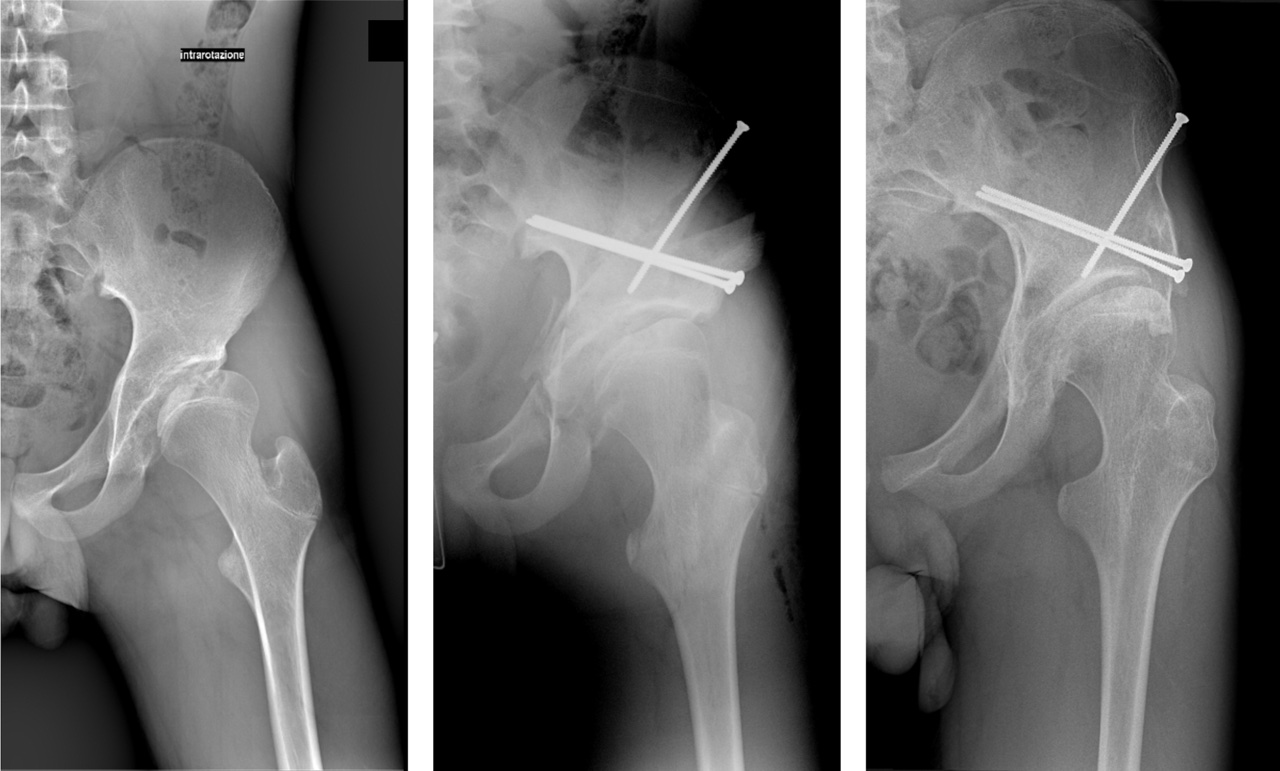

Vista l’ampia varietà della displasia, spesso non si riesce a trattarla con la sola PAO, per cui è necessario associare anche una PFO. L’indicazione varia in base al reperto radiografico nelle proiezioni funzionali dell’anca (abduzione, flessione e intrarotazione).

Partendo dalla RX antero-posteriore possiamo valutare il deficit di copertura acetabolare e lo spazio articolare, per poi passare alle proiezioni funzionali.

La decisione di eseguire come prima procedura la PAO sta nel fatto che nella maggior parte dei casi l’acetabolo displasico presenta un difetto di copertura a livello anteriore, laterale e superiore, per cui il riorientamento dello stesso può già di per sé garantire un miglioramento del quadro, anche se spesso non sufficiente.

La PAO si è dimostrata essere una valida procedura di chirurgia conservativa e la letteratura riporta una sopravvivenza del 75,9% a 10 anni e del 36,5% a 20 anni, dove l’endpoint era la conversione protesica.